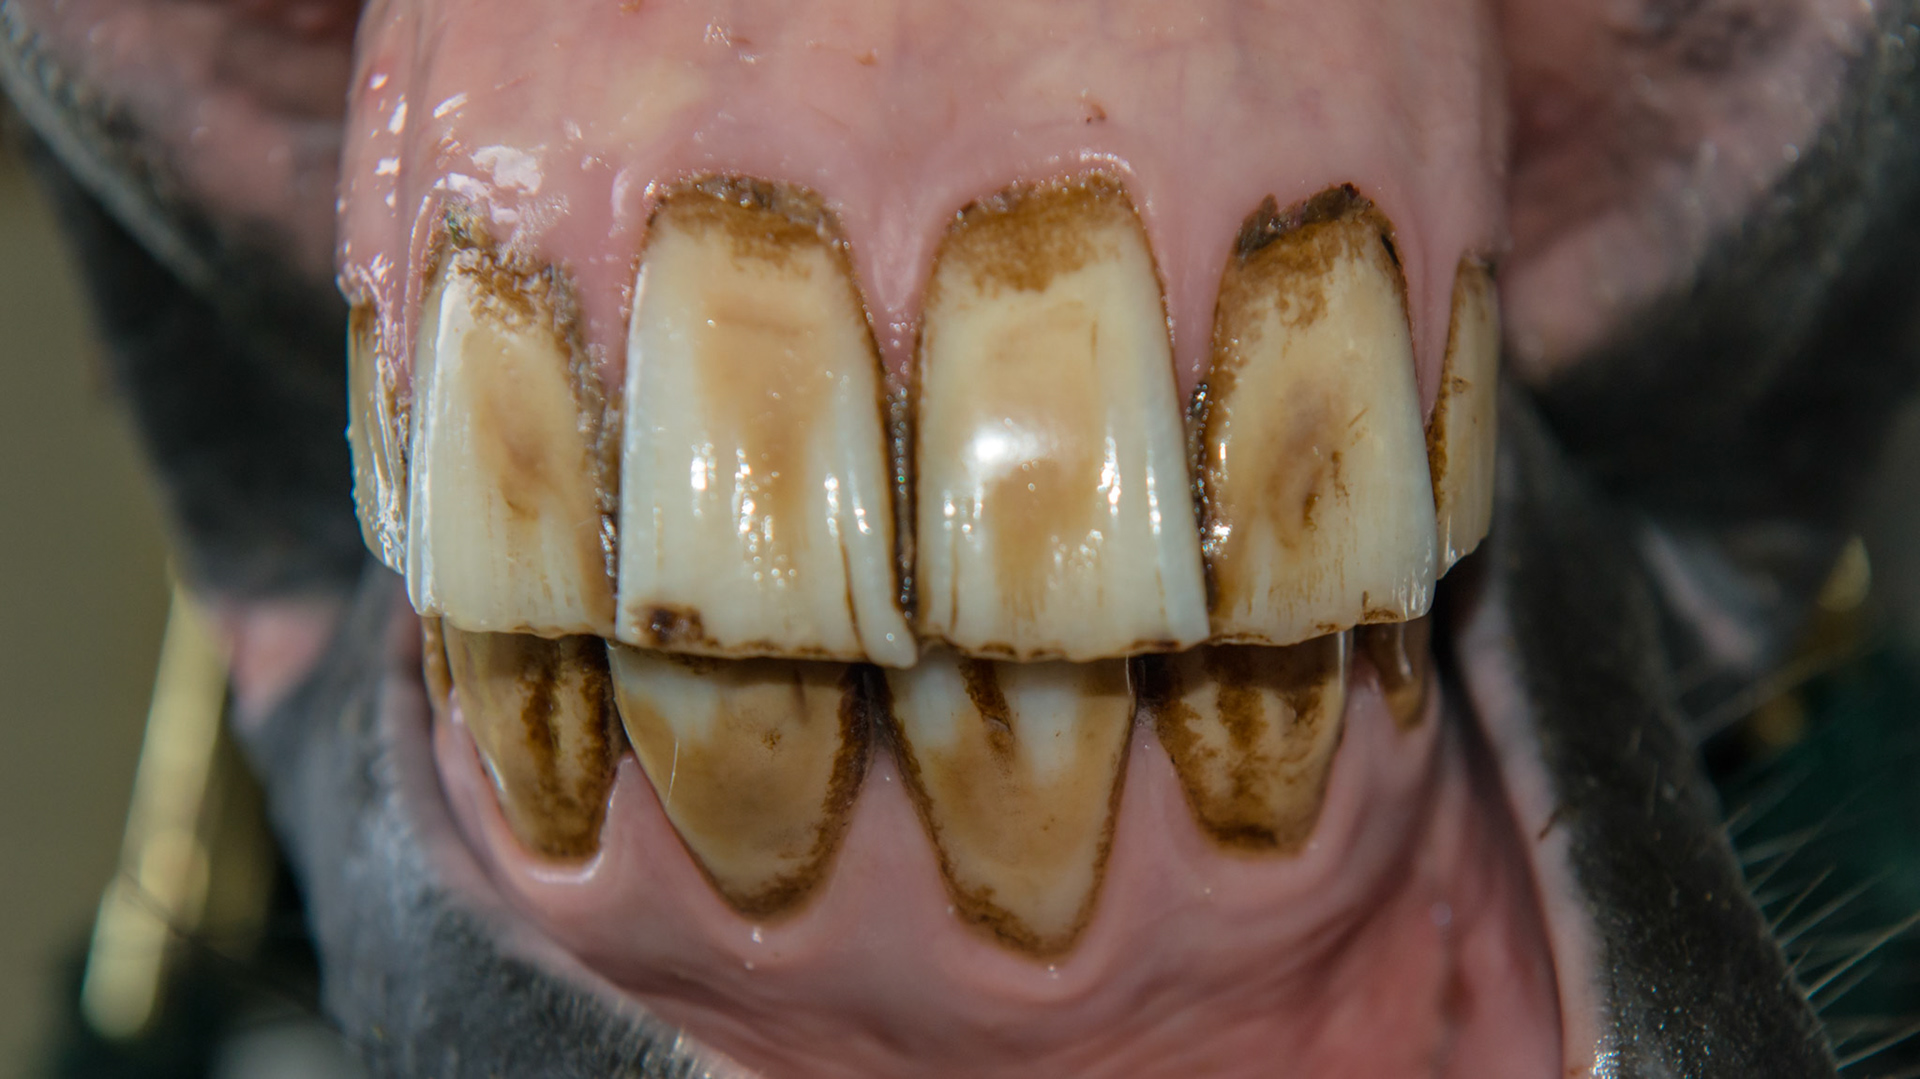

6yr old  Damaged and stained surfaces of all incisors.  Unknown history.